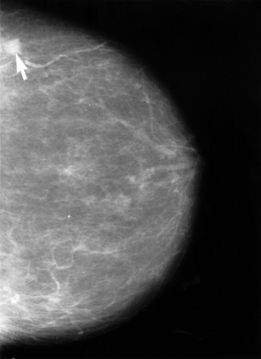

Salli Schwartz maintained rigorous screening routines due to breast cancer’s grip on her family. Her mother and aunt succumbed to the disease, which heightened her commitment to annual checkups. She trusted the state-of-the-art equipment at Summerlin Hospital’s Breast Care Center, which opened in 2011 following a $750,000 investment in digital mammography technology.[1][2]

Federal regulators acted decisively after an inspection by the American College of Radiology uncovered serious deficiencies. The U.S. Food and Drug Administration required Summerlin Hospital to cease mammography operations on December 11, 2025, citing failure to meet clinical image quality standards under the Mammography Quality Standards Act.[1]

A hospital spokesperson affirmed, “We take any concerns very seriously, and quality patient care is our highest priority.” Earlier promotions highlighted the center’s precision, with former CEO Robert Freymuller noting the equipment’s ability to detect even small lesions. State radiation control officials now seek root causes to avert future lapses.